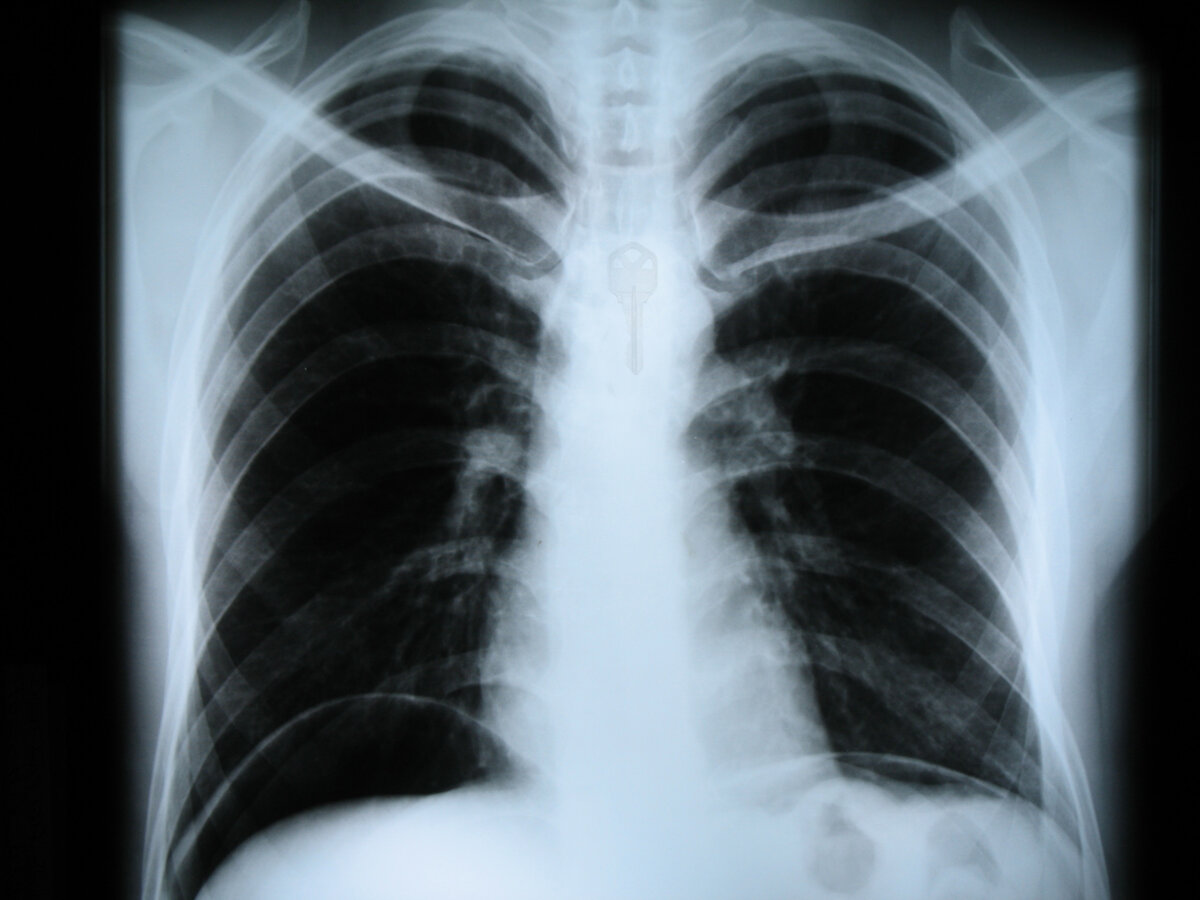

Это было более 10 лет назад, заканчивала я 4й класс. Наступило лето, пора каникул. Что бы меня отпустили гулять мне надо было убрать свою комнату, а делать я этого не хотела. И просто напросто просиживала время которое могла бы потратить с пользой, и игралась с ключом от комнаты. Сидя на кровати я взяла альбом для рисования и решила посмотреть сколько листов изрисовано и что там за рисунки, параллельно беру в рот ключ (а он такой имеет приятный металический привкус) и тут слышу как поднимается в комнату мама, от страха я резко втягиваю воздух и подрываюсь с кровати (убирать то должна в комнате) и случайно необъяснимым до сих пор образом проглатываю ключ. Я в панике, маме сразу об этом не говорю, боюсь что может меня наказать за то что страдала фигней вместо того чтобы убирать да и к тому же проглотила ключ. Бегаю в туалет через каждые пять минут, так как он застрял по пути в желудок, а водой я пыталась его протолкнуть дальше так как очень не приятные ощущения были. Спустя небольшое количество времени, мама заметила мои метания, и начала спрашивать что случилось, я захлебываясь слезами говорит что проглотила ключ от комнаты. Мама в шоке смеясь заводит меня в комнату и говорит папе, что меня может лучше перекрасить (была блондинкой) , папа уже привык что со мной постоянно что то случается, спрашивает что на этот раз, мама рассказывает и доужинав папа со мной собирается и едет в горбольницу. Там меня уже все знают, ждут пока еще с распростертыми руками😂 делают рентген и показывают моим родителям, на рентгене такое ощущение как будто ключик у меня на шее на веревке весит. Оставляют меня до вечера , родителям говорят что нужен гастроэнтеролог и зонд, через который можно проверить на каком этапе и где находится ключ, а гастроэнтеролог будет только через несколько дней, предлагают повезти меня в Симферополь в детскую больницу. Едем значит в Симферополь с Ялты на машине, приезжаем очень поздно в больницу, места в детском отделении все заняты, мне нашли какую то детскую кровать и поставили в одной из палат. Провела я пару дней в больнице, сделали мне проверку этим зондом, обнаружили гастрит, и сказали что ключ уже попал в желудок так как в пищеводе его уже нет, и есть вероятность что выйдет естественным путем. Сделав через несколько дней конечный рентген, нигде его не обнаружили, меня выписали и я отправилась домой. И это не последний мой визит в больницы